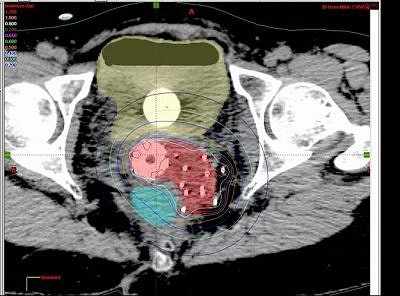

| Interstitial reconstruction, MR (above) versus CT (below). Patient must be imaged with legs down. |

The patients' legs were then brought down and they were reimaged for the CT simulation. "We learned that it was very important to image with the legs down. There was substantial movement with the legs down. But once we figured that out, we were able to perfectly reconstruct the images so that the catheters lined up on MR," Viswanathan said.

Based on the DVH analysis -- done with CT volumes because that is the standard, Viswanathan added -- the median tumor volume was 80 cc. The median V150 was 60%, the median V90 was 82%, and the median V95 was 90%.

"For bladder and rectal DVHs, we saw that the median bladder total volume was 68 cc. We then calculated the 2-cc and 5-cc percent-of-treatment to the bladder volume and it was 80% and 70%, respectively," she said. "The median rectal volume was contoured for 55 cc and we saw that the 2-cc and 5-cc volumes were 90% and 80% of our prescription."